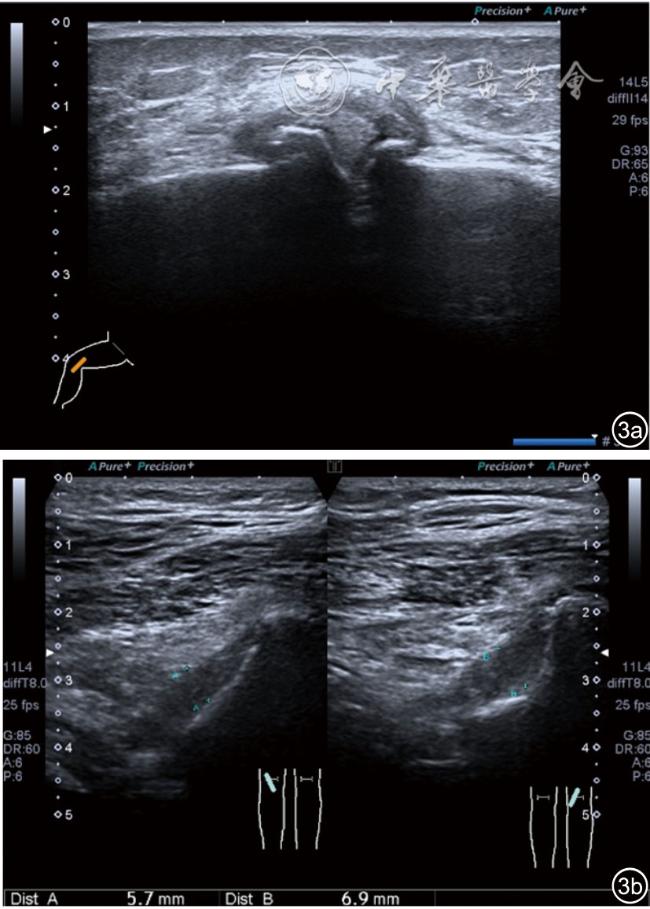

1.关节内表现。(1)骨改变。表现为骨末端或关节周缘出现的骨质局部突起改变,其后方伴或不伴有声影,多见于膝关节内侧缘和外侧缘(图1)。(2)软骨改变。股骨关节面改变可以在长轴及短轴切面显示,嘱患者屈曲膝关节,足平置于检查床,股骨滑车及股骨髁上半部分的关节面即可轻松显示。超声探查可见股骨负重面关节软骨发生不同程度的改变,轻者关节软骨浅侧边界模糊,重者可见关节软骨薄、缺失,软骨下骨缺损改变(图2)。(3)半月板外突。一般内侧半月板突出多见,外侧半月板突出比较少。半月板可见不同程度的外突,同时伴有膝内侧副韧带向外移位(图3)。半月板外周缘性滑脱是指半月板突出超出胫骨平台边缘的距离≥3 mm,其可引起一系列临床症状,早期诊断、早期治疗可以预防骨关节的进一步损伤。(4)交叉韧带损伤。可见前后交叉韧带增粗,回声减低(图4)。(5)髌上囊积液。膝关节是最容易发生积液的关节之一。患者仰卧位,关节积液最常见于膝关节上外侧,因为关节囊向髌股关节上外侧突出。髌上囊积液采用10~18 MHz的高频线阵探头于股四头肌腱纵断面及横断面扫查均可显示,探头频率取决于患者体型。超声可见低回声积液,慢性可伴有丛状滑膜增生(图5)。(6)脂肪垫水肿。脂肪垫在髌骨附着点处回声增强、增厚(图6)。

图3 半月板突出超声图像

3.超声半定量评估。(1)骨赘超声半定量评估:患者仰卧位,膝关节伸直,探头纵切面置于膝关节内侧与外侧,自前向后移动探头以进行全面扫查。测量骨赘的厚度,并进行半定量分析。0级:无骨赘;1级:小骨赘,厚度<2 mm;2级:中等骨赘,厚度2.1~4.0 mm;3级:大骨赘,厚度>4.0 mm。(2)关节软骨超声半定量评估:患者仰卧位,膝关节完全屈曲。探头置于骨上方,检查股骨内侧髁、外侧髁和股骨滑车处关节软骨三个部位,分别进行横切面和纵切面检查,从近侧向远侧做全面扫查。检查时声束要垂直于股骨表面。关节软骨可按病变严重程度分为四级。0级:关节软骨呈均匀的无回声带,其浅侧和深侧边界清晰。1级:关节软骨浅侧边界不清和(或)内部回声增高。2级:①2A级,关节软骨局部变薄,缺损厚度<50%;②2B级,关节软骨局部变薄,缺损厚度>50%,但<100%。3级:关节软骨局部完全消失,伴或不伴有软骨下骨病变。(3)半月板突出分度:半月板外周缘与胫骨平台边缘之间的距离≥3 mm的突出视为病理变化,诊断为半月板周缘滑脱。按照突出程度分为三度:Ⅰ度,半月板外周缘与胫骨平台边缘之间的距离3~5 mm;Ⅱ度,半月板外周缘与胫骨平台边缘之间的距离>5~8 mm;Ⅲ度,半月板外周缘与胫骨平台边缘之间的距离8 mm以上。